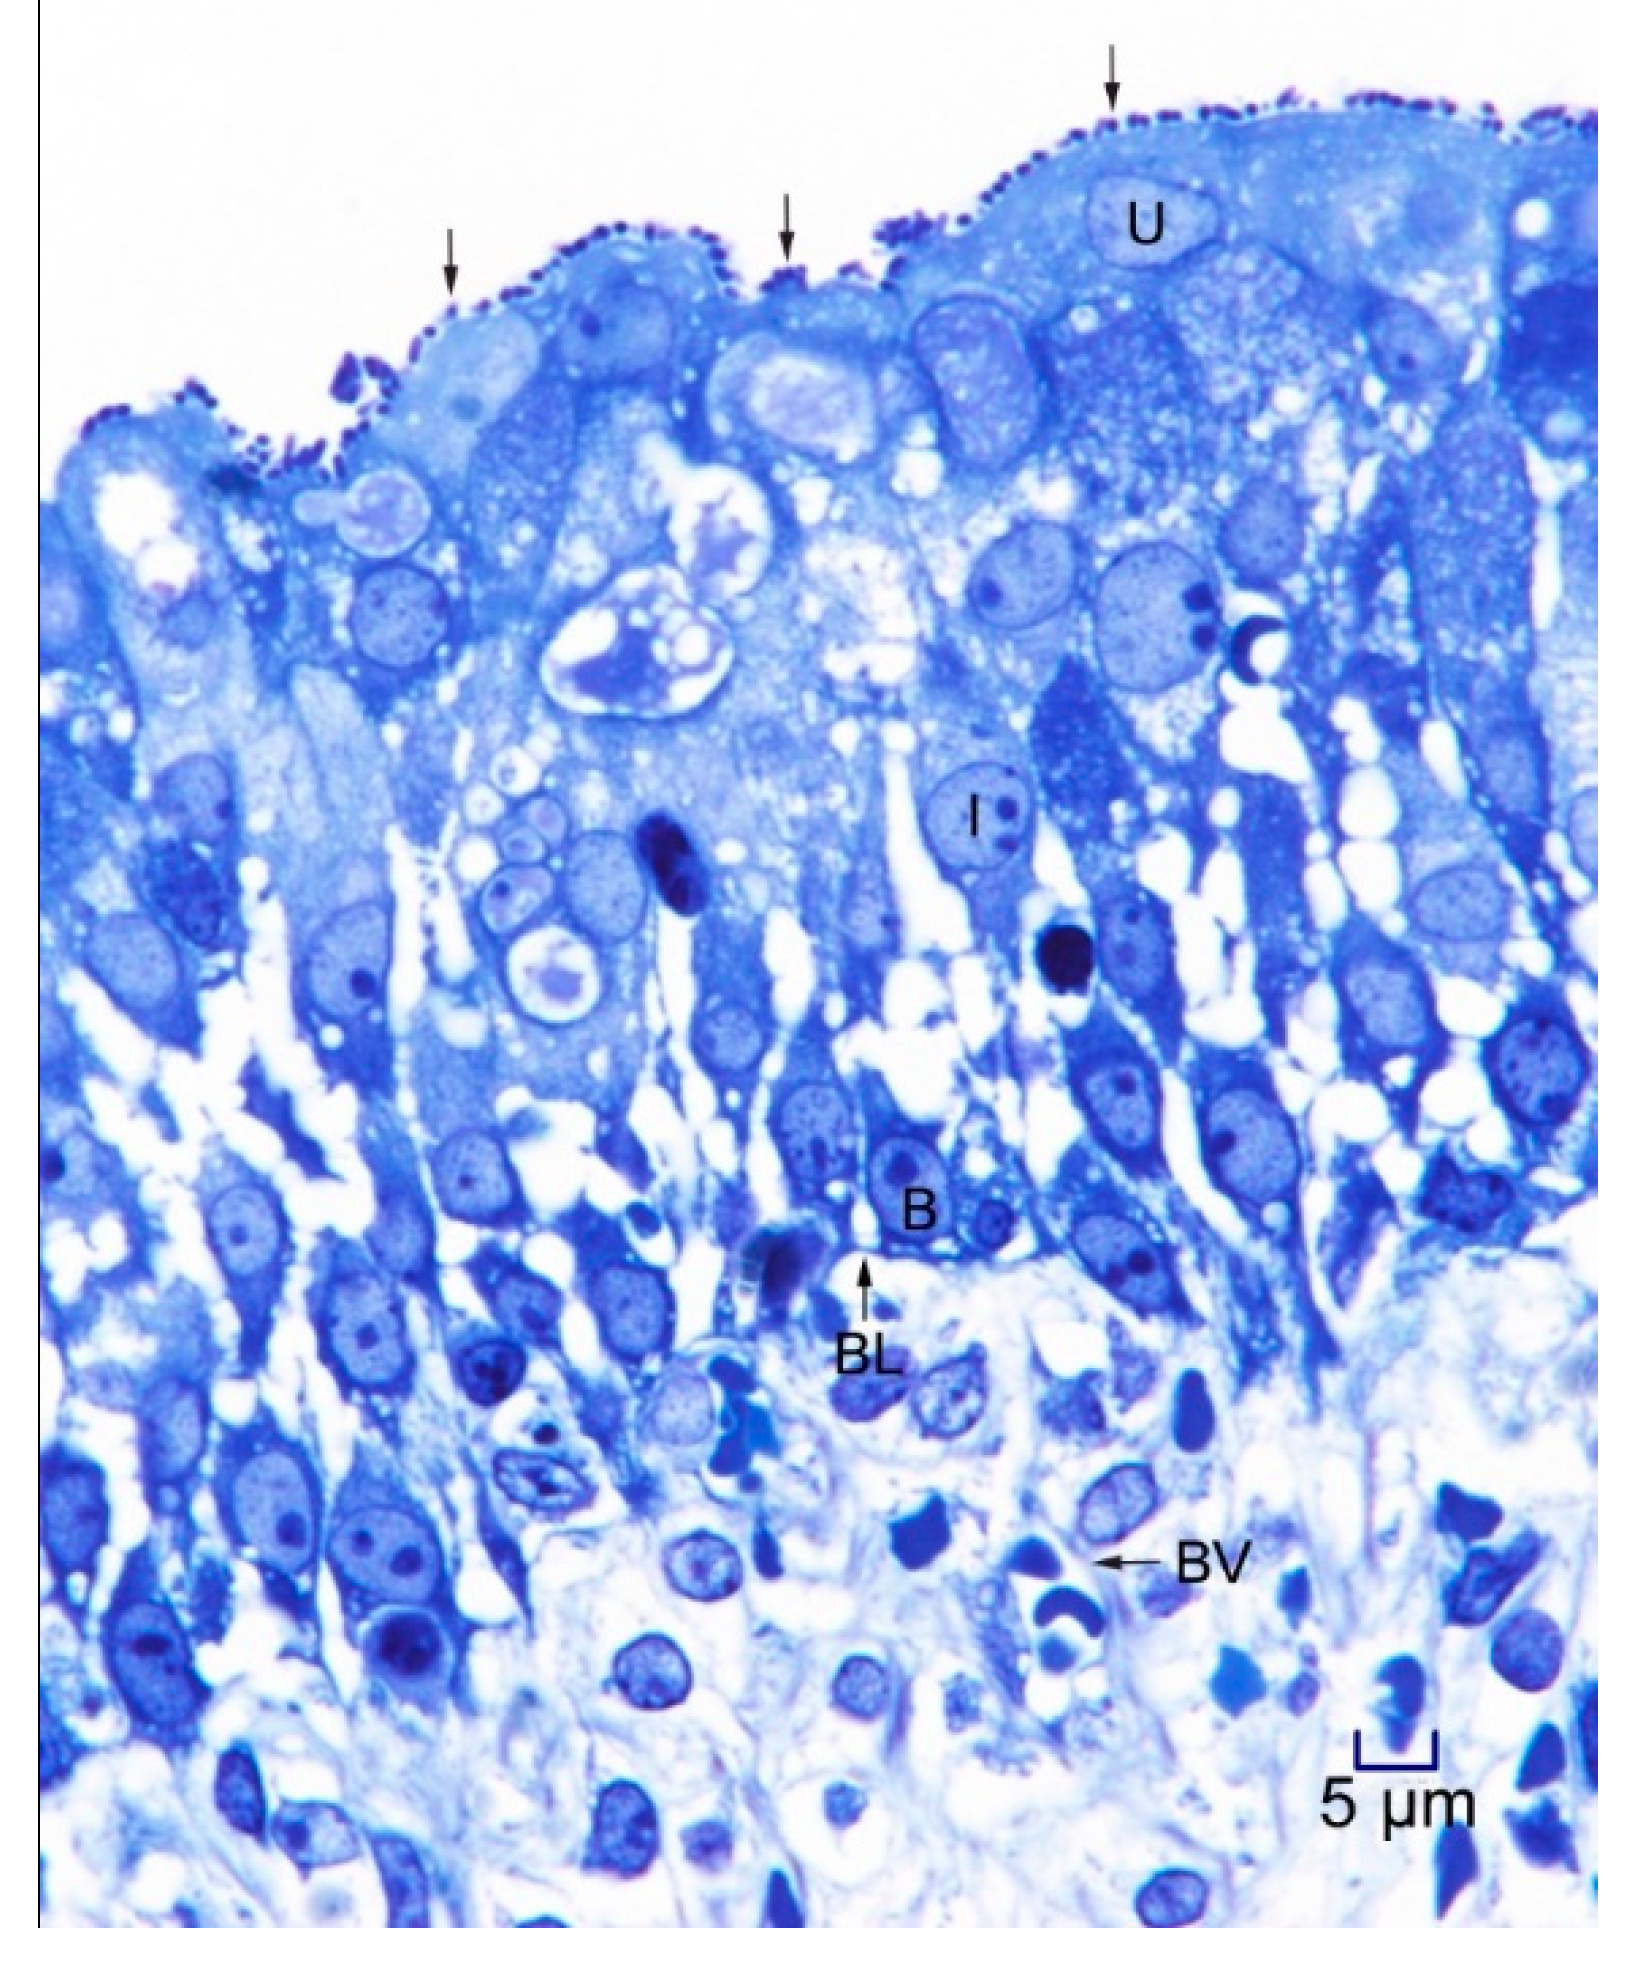

In 1-μm thick Araldite sections of urinary bladder prepared from tissues originally contained within the paraffin blocks [25], bacteria were detected only in piglet 15627 (Figure 1). In this piglet, in which bladder sections were oriented such that all three cell layers (basal, intermediate and superficial or umbrella) of the urothelium [26,27,28,29] were visible, bacteria, corresponding to bovine-origin strain 2891, were diffusely adherent to the apical surfaces of umbrella cells. By TEM, bacterial cells were found intimately attached to pedestals (Figure 2, Figure 3 and Figure 4). Some bacterial cells appeared to be attached to microplicae, preceding pedestal formation (Figure 4).

Figure 2.

Transmission electron photomicrograph of a thin section of a superficial epithelial (umbrella) cell of the urinary bladder of piglet 15627, 8 days PI with bovine-origin strain 2891. Five bacteria are seen in the section, with one attached to an actin pedestal near the center of the figure. Bar = 500 nm.

Morphologically, the pedestals to which bacteria in the urinary bladder of piglet 15627 were intimately attached were consistent with actin pedestals induced by EHEC and enteropathogenic E. coli (EPEC) in intestinal epithelium [24]. To our knowledge, this is the first report of intimate bacterial adherence and actin pedestals in the uroepithelium in any species. Staley et al. [30] first reported these lesions in 1969, describing them as attachment and microvillous exfoliation in ileal enterocytes of newborn, cesarean-derived piglets intragastrically inoculated with an E. coli strain belonging to a classical EPEC serotype, O55:H7. Takeuchi et al. [31] later described these lesions as occurring in rabbits inoculated with RDEC-1, a rabbit-origin O15:NM E. coli later classified as an EPEC [23]. Soon thereafter, the lesions were recognized in human infants with EPEC infection [32,33]. Moon et al. coined the term “attaching and effacing” to describe intimate attachment and effacement of microvilli in the intestinal epithelium of piglets and rabbits by EPEC [23]. Knutton et al. [34] first determined that the electron-dense material underlying the bacteria within the pedestals was filamentous actin. Over the past 50 years since the initial report by Staley et al. [30], numerous studies, many at the molecular level, have elucidated key bacterial and host factors involved in the pathogenesis of intimate attachment and pedestal formation [29].